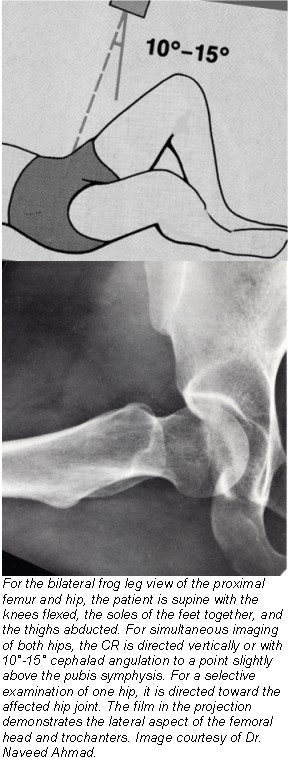

- For a bilateral projection, both hips and knees are flexed approximately 90°. Have the patient draw the feet up as much as possible. After correctly centering the cassette 1 inch (2.5 cm) superior to the pubic symphysis, abduct both thighs approximately 45° from the vertical plane to place the long axis of femoral necks parallel with the plane of the cassette. Ensure that both thighs are abducted the same amount and that pelvis is not rotated (equal distance of both ASIS to the tabletop). Have the patient turn their feet to brace the soles against one another for support.

- For unilateral frog leg projection center the ASIS of the affected side to the midline of the grid. Ask the patient to flex the hip and knee of the affected side, then abduct the thigh laterally, approximately 45°. Have the patient draw the foot up to the opposite knee as much as possible so that the sole of the foot is against the opposite knee. The pelvis may rotate slightly in a unilateral projection.

- Carefully palpate the superior portion of iliac crest and direct the CR to a point 3 inches (7.5 cm) below the level of the ASIS (1 inch or 2.5 cm above symphysis pubis). For the unilateral position, direct the CR to the femoral neck.

![]() |

- Femoral heads and necks, acetabulum, and trochanteric areas should be visible on a single radiograph.

- No rotation is evidenced by symmetric appearance of the two obturator foramina and pelvic bones. The lesser trochanters should appear equal in size as projected on the medial margins of the femora. The greater trochanters are superimposed over the femoral necks.

- The femoral heads and necks and trochanters should appear symmetric if both thighs are abducted equally.